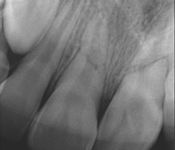

Pictured: Preoperative, Retreatment, Apicoectomy

and 5 Year Recall

Our patient required root canal retreatment. After an apicoectomy, the removal of the root tip and the infected tissue, there was complete bone healing in the 5 year recall.